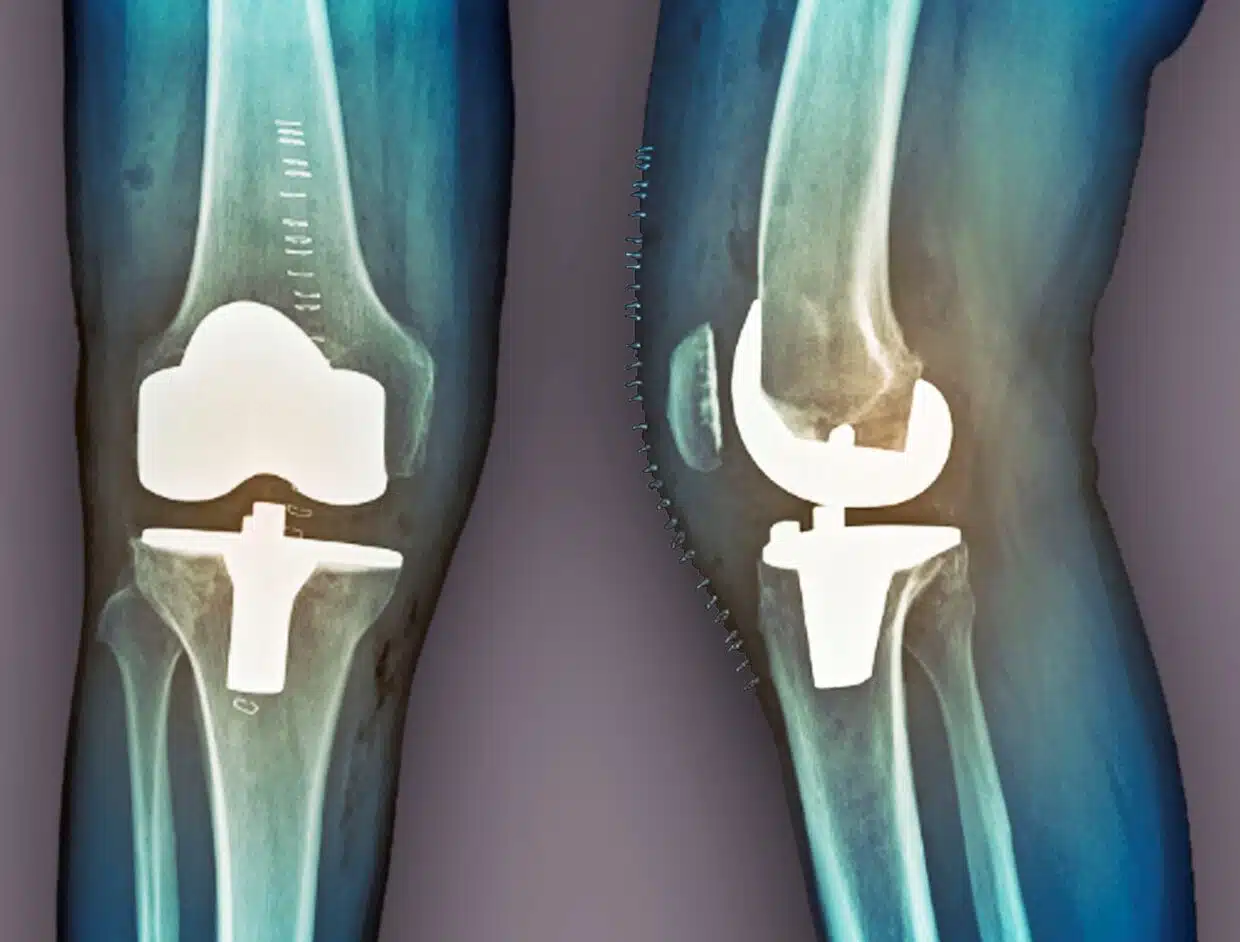

عملية تغيير مفصل الركبة تعد من العمليات الهامة التي يلجأ لها بعض المرضى في حالة عدم استجابة الجسم للتمارين أو للعلاج الدوائي حتى يتمكن المريض من التخلص من الشعور بالألم الذي يعاني منه.

- نوع المفصل الذي سيقوم الطبيب بوضعه بدلاً من المفصل التالف سواء كان كلي أو جزئي.